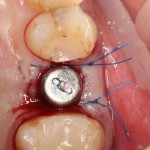

Прежде, чем приступить к аугментации (пластике) лунок зубов, мы подготовили лунки для имплантатов. В таких клинических случаях нет необходимости в использовании шаблона. Вместо этого, мы применяем общепринятые правила позиционирования и соблюдаем рекомендации производителя по хирургическому протоколу:

В процессе ирригации лунки промываются, что позволило нам еще раз подтвердить ранее сделанные выводы. С помощью аналогов имплантатов, входящих в хирургический набор Xive, мы проверили возможность стабилизации имплантатов в будущих лунках. Исходя из правил подбора и позиционирования имплантатов (я очень рекомендую почитать об этом здесь>>) мы остановились на Xive S диаметром 3,4 мм и длиной 13 мм.

Подготовка двух лунок для имплантатов занимает около 10 минут.